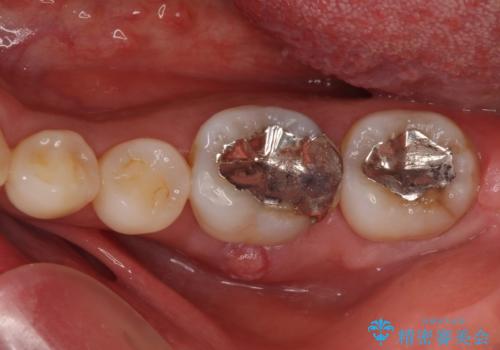

- 左下奥に、咬んだときの痛みを感じて来院された患者様です。

排膿路が形成されている歯は既に失活しており、根管治療が必要になっていました。

根管治療などを行った後に、オールセラミッククラウンにて補綴することとしました。